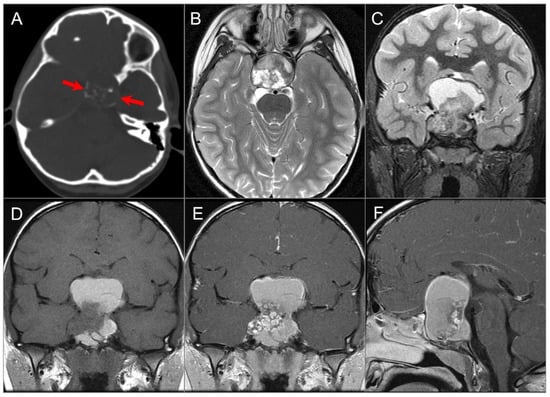

4.4.1. Chordoma